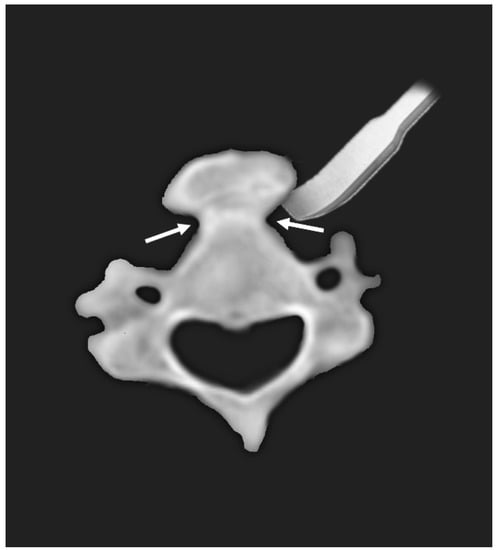

In the present study, we report two cases of dysphagia due to anterior osteophytes with underlying DISH. The patients were successfully treated with osteophyte removal via anterolateral approach. Based on axial images of preoperative CT, the osteophytes could be removed easily using an osteotome starting from the bottleneck point between the vertebral body and the excrescent osteophyte (Figure 3). This case report is a unique study focusing on the surgical aspect of treatment.

Figure 3.

Diagram of typical axial appearance of anterior bony excrescence. Using the bottleneck point (arrows) between the vertebral body and bony excrescence, anterior osteophytes can be easily removed using an osteotome.